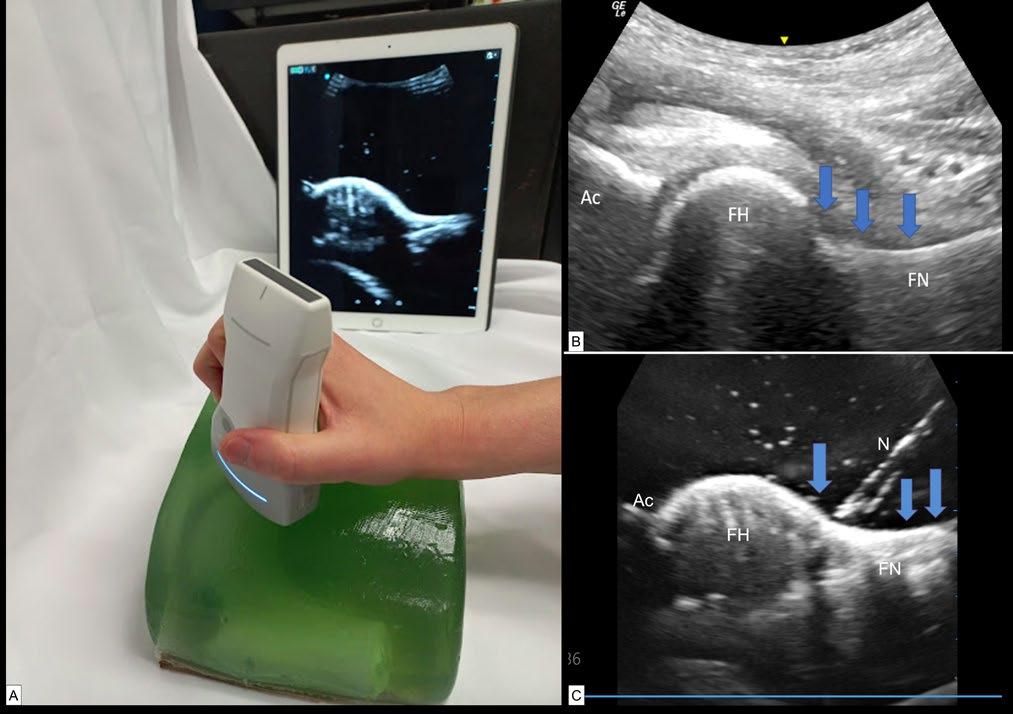

3. Department of Endocrinology and Diabetes, Salford Royal Hospital, UK

4. The School of Medicine and Manchester Academic Health Sciences Centre, Manchester University, UK

5. Department of Diabetes & Endocrinology, Surrey & Sussex Healthcare NHS Trust, Redhill, UK *Correspondence to m.b.whyte@surrey.ac.uk

Disclosure:

Field has received consultancy and/or lecture fees, and/ or support to attend conferences from Abbot Diabetes, AstraZeneca, Boehringer Ingelheim, Eli Lilly and Company, Gilead, GlaxoSmithKline, Janssen, Medtronic, MSD, Napp, Novo Nordisk, and Sanofi. The other authors have declared no conflicts of interest.

Received: 16.08.22

Accepted: 15.09.22

Keywords: Diabetes, incretin system, therapy, treatment.

Citation: EMJ Innov. 2022. DOI/10.33590/emjinnov/10115628. https://doi. org/10.33590/emjinnov/10115628.

Abstract

The scientific community has made great strides in responding to the huge public health problems of obesity and diabetes with the discovery of the incretin system and the development of glucagon-like peptide 1 analogues. These have shown clinical efficacy in randomised controlled trials and observational data from realworld evidence; however, a ‘treatment gap’ remains between the therapeutic success of these molecules and the outcomes achieved with bariatric surgery. To help address this, dual incretins are being developed. These combine glucagon-like peptide 1 action with that of either glucose-dependent insulinotropic peptide or glucagon. This narrative review charts the development of incretin therapy, and the dual agonists for treatment of Type 2 diabetes and obesity.

Key Points

1. Agonists of the incretin glucagon-like peptide-1 (GLP-1) have established efficacy for glycaemic reduction, weight loss, and cardiovascular risk modification; however, some patients may still not achieve metabolic targets and efficacy remains considerably less than that seen with bariatric surgery.

Creative Commons Attribution-Non Commercial 4.0 ● February 2023 ● Innovations 47

Review

2. In recent years, dual agonists of the incretin system have been tested in pre-clinical and early-phase clinical trials, with the glucose-dependent insulinotropic polypeptide and GLP-1 co-agonist, tirzepatide, recently approved for clinical use. This provides near double the weight loss to GLP-1 agonists and significant glucose lowering, as well as promising efficacy in non-alcoholic fatty liver disease. Future prospects include triple agonists of glucagon, glucose-dependent insulinotropic polypeptide, and GLP-1.

3. This article highlights the evolving understanding of the incretin system over the years, leading to the development of multi-agonists, which hold the potential for marked metabolic benefits, mimicking that seen with bariatric surgery.

INTRODUCTION

The identification of the incretin system as consisting of hormones located in the gastrointestinal mucosa, that have insulinotropic action; and its subsequent exploitation in the form of glucagon-like peptide 1 (GLP-1) receptor agonists (RA) has been a therapeutic success story for Type 2 diabetes (T2D) and obesity management. Nonetheless, therapeutic failure, partly from inability to maximise the dose or persist with the medication because of nausea and vomiting, limits the potential of this class of drugs. The recognition of the contribution of other hormones in the incretin system, with pleiotropic actions, has led to the development of dual agonists, which can maximise metabolic benefits with a lower potential for side-effects. This may help to close the ‘treatment gap’ between the effects of existing drugs and that of bariatric surgery on weight and metabolic parameters.

This narrative review covers the identification and development of incretin therapy for diabetes and obesity, culminating in the recent clinical trials of dual agonist therapy and the future prospect of tri-agonists.

SEARCH METHODOLOGY

The authors searched the English-language literature to identify all relevant studies, regardless of publication status or year of publication. They searched the PubMed and Google scholar databases, combining the terms dual agonist’ OR ‘triple agonist’ OR ‘GIP/GLP-1’ OR ‘[glucagon-like peptide 1]’ PLUS ‘[glucose dependent inhibitory peptide]’ OR ‘glucagon/ GLP-1’ OR ‘dual incretins’. Studies could include pre-clinical or early or late phase human

trials. Additional studies were added by cross referencing the retrieved studies. The last search was performed in July 2022.

DISCOVERY OF INCRETINS

The superiority of enteral, compared to parenteral glucose administration in stimulating insulin secretion in humans, was first described in 1964 by McIntyre et al.1 This paper reignited long-dormant interest in the concept of incretins: putative gastrointestinal factors released during meal absorption that might stimulate insulin secretion in a glucose-dependent fashion. Two hormones released by enteroendocrine cells in the gut mucosa were subsequently discovered to be largely responsible for the incretin phenomenon. Glucose-dependent insulinotropic polypeptide (GIP, also known as gastric inhibitory polypeptide) was the first to have its incretin effect demonstrated, by the Canadian team of Dupre et al.2 Identification of the other hormone, GLP-1, was a more complex task because of the difficulty of differentiating it immunologically from other bioactive products and inactive degradation fragments of its precursor, proglucagon. The ability of intravenously infused GLP-1 to stimulate insulin secretion in humans in a glucose-dependent fashion was eventually described by Kreymann et al.3

GLUCAGON-LIKE PEPTIDE-1

Despite being identified later than GIP, GLP-1 quickly became the focus of intensive research, such that fewer than 20 years were to elapse between the description of its incretin effect and the approval of the first highly successful GLP-1 RA drug class for treatment of T2D.4 GLP-1 is released after food intake3 into the

48 Innovations ● February 2023 ● Creative Commons Attribution-Non Commercial 4.0

enterohepatic portal system by L cells located predominantly in the mucosa of the ileum and large bowel.5 The bioactive forms, GLP-1(7–37) and most abundantly, GLP-1(7–36)NH2, are inactivated by dipeptidyl peptidase-4 (DPP4).6 Intravenously infused GLP-1 slows gastric emptying,7 reduces appetite and food intake,8 and suppresses glucagon (GCG) secretion at normal and high blood glucose concentrations, but not during hypoglycaemia.9 Further evidence for the physiological role of GLP-1 in regulating GCG secretion accrued from studies showing that exendin (9–39), an antagonist of the GLP1 receptor, impairs oral glucose tolerance10 by disinhibiting GCG secretion when blood glucose concentration is normal or elevated.11 As a result, GLP-1 RAs reduce hyperglycaemia with little risk of hypoglycaemic episodes.

Development of Drugs Acting on the Glucagon-Like Peptide-1 Receptor

Exendin-4, a peptide component of the venom of the Gila monster (Heloderma suspectum), has approximately 50% structural homology to GLP-1(7–36)NH2 and is a DPP4-resistant agonist at the GLP-1 receptor (GLP-1R).12 As this confers a much longer half-life than that of native sequence GLP-1 (hours rather than minutes), the development of GLP-1 RAs has proceeded down two paths: as analogues of either human GLP-1, or of exendin-4.

Human GLP-1-analogues that have come to market include liraglutide, dulaglutide, semaglutide, and albiglutide (the last has been withdrawn). Marketed drugs based on exendin-4 are exenatide and lixisenatide (Figure 1).12,13 Modifications to prolong the half-life of GLP-1 RAs include sequence substitutions conferring resistance to DPP-4, along with acylation (liraglutide and semaglutide), covalent bonding to modified Ig fragment crystallisable domain (dulaglutide), or covalent bonding to albumin. These various approaches delay clearance by the kidney.

Notwithstanding their resistance to degradation by DPP-4, exendin-4-based GLP-1 RAs require daily (lixisenatide) or twice daily (exenatide) dosing without further modification. A weekly version of exenatide (Bydureon [AstraZeneca, Cambridge, UK]) has therefore been developed, in which co-formulation with poly(D,L-lactideco-glycolide), a material similar to that used in soluble sutures, slows release of drug from the injection site depot.12,13

Regulatory approval for the first GLP-1 RA drug for the treatment of T2D was issued in 2005 and since then GLP-1 RAs have proved highly clinically effective.12,13 Although the original approval was largely based on the potent glucose-dependent insulinotropic properties

Creative Commons Attribution-Non Commercial 4.0 ● February 2023 ● Innovations 49

GLP-1: glucagon-like peptide 1. Review

Figure 1: Classification of glucagon-like peptide 1 receptor agonists.

of GLP-1R activation on pancreatic β-cells, it has become clear that the GLP-1R is expressed on a variety of other tissues, which produce a range of biological effects across diverse organ systems (Figure 2).14

Early research on the therapeutic potential of GLP-1 was directed towards glucose regulation in diabetes but was extended, through concurrent observations of body weight lowering to obesity management. Weight reduction may result from activation of vagal and cerebral GLP-1Rs, leading to appetite suppression. Average weight loss achieved with GLP-1 RA at doses suitable for treating T2D is around 5 kg.12,15 GLP-1 RAs have been licenced (at higher doses than those used for diabetes) for the treatment of obesity. The European Medicine Agency (EMA) approved daily liraglutide (3.0 mg) and weekly semaglutide (1.7 or 2.4 mg) for this indication in 2021.

Studies Showing the Efficacy of Glucagon-Like Peptide-1 Receptor Agonists

In addition to lowering HbA1c, GLP-1 RAs improve traditional cardiovascular disease risk factors such as obesity and hypertension, whilst also exerting anti-inflammatory and antiatherosclerotic effects, and having positive direct modulatory effects on endothelial function.12

Several large, randomised trials have shown that GLP-1 RAs reduce major adverse cardiovascular events (MACE) compared with placebo. These include LEADER (liraglutide), REWIND (dulaglutide), and SUSTAIN-6 (semaglutide);12,16 however, no statistical differences in MACE outcomes were found in ELIXA (lixisenatide) or EXSCEL (exenatide). Meta-analysis of renal outcomes shows GLP-1 RAs reduce renal events by 15%, primarily through prevention of albuminuria, and mortality by 11%, with no difference between agents;12,16 however, there is a lack of data comparing these GLP-1 RA outcomes versus other glucose lowering therapies.

COMPARATIVE EFFECTS OF GLUCAGON-LIKE PEPTIDE-1 AND GLUCOSE-DEPENDENT INSULINOTROPIC POLYPEPTIDE

Both GLP-1 and GIP have profound effects on energy metabolism and body weight (Table 1). Whilst both have significant incretin effect on insulin secretion, their effects on GCG release differ. GLP-1, but not GIP, slows gastric emptying, which further reduces post-meal glycaemic increments. As described above, GLP-1 inhibits appetite and food intake, resulting in weight loss upon chronic administration; however, GIP

50 Innovations ● February 2023 ● Creative Commons Attribution-Non Commercial 4.0

GLP-1: glucagon-like peptide 1.

Figure 2: Pleiotropic actions of glucagon-like peptide 1.

is generally thought to have no effects on food intake.17 GIP, but not GLP-1, increases triglyceride storage in white adipose tissue via stimulation of insulin secretion, and through vasodilation of adipose vascular tissue, as well as inhibiting bone resorption. GIP is, therefore, an anabolic hormone that inhibits lipolysis, and stimulates lipogenesis and bone formation. Increased GIP levels are observed in obesity, as fat is a potent stimulus of GIP secretion.17

GLUCOSE-DEPENDENT INSULINOTROPIC POLYPEPTIDE

There was little enthusiasm for therapeutic use of GIP in the years after its discovery because GIP infusions had little effect on insulin secretion and appetite regulation in T2D.17 GIP stimulates GCG secretion and potentiates insulin secretion during hyperglycaemia (Figure 3A);17 however, the insulinotropic effect of GIP is severely curtailed in T2D.18,19 Yet, the glucagonotropic effect of GIP prevails, even during hyperglycaemia (Figure 3B).20 Combined infusions of GIP and GLP-1 have additive insulinotropic effects in the non-diabetic state,21 and resistance to GIP-induced insulin secretion

in T2D can be reduced by a short period (weeks) of intensive glucose-lowering treatment (Figure 3C).17,22, This provides a rationale for using GLP-1 together with GIP agonism, as GLP-1 may lower glucose sufficiently to unmask the incretin effect of GIP, while GLP-1 action may overcome the potentiating effect of GIP on GCG secretion. Initial disinterest in the use of GIP has abated and the most prominent, recent approaches to dual incretins are unimolecular combinations of GIP with GLP-1R agonism.

RATIONALE FOR DUAL OR TRIPLE AGONISTS

As described above, GLP-1 RA have proven efficacy and their use has increased steadily since their launch in 2005.12-14 They are effective for glycaemic control and lead to weight loss that far exceeds that of the intestinal lipase inhibitor, orlistat;23 however, there remains a significant treatment gap in weight management between that attained with GLP-1 RA and bariatric surgery (Figure 4). The human body’s energy balance is governed through much more than a single hormone and it would be anticipated that combinatorial approaches will help close

Creative Commons Attribution-Non Commercial 4.0 ● February 2023 ● Innovations 51

Site GLP-1 GIP Pancreas β-cells ↑Insulin synthesis ↑Insulin synthesis

secretion ↑Insulin secretion

proliferation ↑Cell proliferation ↑Glucose sensing ↑Glucose sensing α-cells ↓GCG secretion ↑GCG secretion Brain ↑Satiety N/A ↓Appetite Gastrointestinal ↓GI motility N/A ↓Gastric emptying Adipose tissue N/A ↑Lipolysis ↑Fatty acid synthesis ?Anti-lipogenic effect

Table 1: Metabolic effects of glucose-dependent insulinotropic peptide and glucacon-like peptide 1.

↑Insulin

↑Cell

GCG: glucagon; GI: gastrointestinal; GIP: glucose-dependent insulinotropic peptide; GLP-1: glucagon-like peptide 1.

the treatment gap for obesity. Furthermore, the tolerability of GLP-1 RA is often dose-limiting. The most widely reported clinical side-effect of GLP-1 therapy is nausea, which is seen in 13–36% (lower incidence in once weekly preparations).13 Drug surveys have shown that most patients remain at the starting dose.24 There is a need for drugs with equal or better efficacy and a side effect profile that allows dose maximisation. By combining hormones in this way, the dose of individual hormones can be reduced, widening the therapeutic window, and avoiding toxicity.25

Glucagon-Like Peptide-1 and GlucoseDependent Insulinotropic Polypeptide Dual Agonists

A molecule that attracted early interest was NNC0090-2746 (also known as MAR709, RO6811135, and RG7697). This is a balanced GIP and GLP-1 RA, the development of which has been pursued, unsuccessfully to date, by several pharmaceutical companies.26,27 A Phase II trial in T2D showed a 1% reduction in HbA1c (Diabetes Control and Complications Trial units) and approximately 1.7% body weight reduction over

12 weeks, in comparison to placebo, but a further comparison to an open-label liraglutide active treatment control group was less impressive.26

The drug that has advanced furthest through development, in fact all the way to market, is Eli Lilly and Company’s (Indianapolis, Indiana, USA) tirzepatide (LY3298176), a unimolecular dual GIP/GLP-1 RA. It has comparable GIP receptor binding affinity to native GIP but fivetimes lower GLP-1R affinity than native GLP-1 and is thus an imbalanced co-agonist.28 This imbalance may allow maximisation of effect on the GIP pathway while minimising GLP-1-related tolerability issues; however, a further possibility has recently come to light. Experiments in islet cell models have shown that intracellular signalling after GLP-1R agonist binding occurs via two pathways, one of which (cyclic adenosine monophosphate generation) enhances insulin release, while the other (β-arrestin recruitment) causes GLP-1R receptor

Intriguingly, the intracellular consequences of tirzepatide binding at the GLP-1R seem to be peculiarly biased towards cyclic adenosine monophosphate generation, at the expense of

52 Innovations ● February 2023 ● Creative Commons Attribution-Non Commercial 4.0

internalisation, and hence reduces cellular sensitivity to ligand.29 Figure 3: Effect of hyperglycaemia and diabetes on glucose-dependent insulinotropic peptide’s insulinotropic action.

A B C Review

A) Experimental (acute) hyperglycaemia. B) Hyperglycaemia in established diabetes. C) Sustained normoglycaemia in diabetes. GIP: glucose-dependent insulinotropic peptide.

β-arrestin recruitment. However, tirzepatide also has low efficacy to induce GLP-1R internalisation, perhaps by its limited ability to recruit β-arrestin. Therefore, the GLP-1R-mediated insulinotropic effect of tirzepatide might be enhanced not just by GIP receptor activity but also by bias in its interaction with the GLP-1R.29

Tirzepatide consists of 39 amino acids, with a C20 unsaturated di-acid acyl chain. The side chain binds to albumin, thereby prolonging the half-life, allowing weekly dosing. Phase II findings published in 2018 were promising, with tirzepatide showing dose-dependent effects on glucose levels and bodyweight.30 It outperformed dulaglutide 1.5 mg/day at the highest doses, albeit in a small group of study participants.

The Phase III trials have been testing tirzepatide as monotherapy, as an add-on to other treatments, and against established glucoselowering drugs in people with T2D, as well as a weight-loss agent in people with diabetes and obesity. The clinical trial data available have yielded impressive results on glucose control and weight loss (Table 2).31-41 It may be that improvements in islet function and insulin sensitivity with tirzepatide (compared to GLP1) account for the greater benefits in glucose regulation.42 Cardiovascular effects are being

examined in the SUMMIT trial.38 This will test whether people with obesity plus heart failure with preserved ejection fraction, randomised to tirzepatide or placebo for 52 weeks, improve a composite endpoint of mortality, heart failure events, exercise capacity, and heart failure symptoms.43 As a result of the evidence from Phase III trials, the U.S. Food and Drug Administration (FDA)-approved tirzepatide (Mounjaro™ [Eli Lilly and Company]) for the treatment of adults with T2D in May 2022.

Glucagon-Like Peptide-1 and Glucagon Dual Agonists

The well-known action of GCG is to increase blood glucose (hence ‘glucagon’ being a portmanteau of ‘glucose agonist’). It does so through stimulation of gluconeogenesis and glycogenolysis in the liver. GCG has additional effects including the modulation of food intake and satiety, lipolysis, fatty acid oxidation, ketogenesis, and increased energy expenditure.44 These latter metabolic effects make GCG attractive as an anti-obesity agent, but the applicability, especially in T2D, is complicated by the inherent risk of inducing hyperglycaemia.

Further characterisation of the GCG-like family of peptides led to the discovery of an endogenous

Creative Commons Attribution-Non Commercial 4.0 ● February 2023 ● Innovations 53

Figure 4. Treatment gap in obesity therapy.

Treatment

GLP-1 RA+lifestyle Review

GLP-1 RA: glucagon-like peptide 1 receptor agonists.

gap

Diabetes trials

SURPASS-131

Weekly tirzepatide 5, 10, and 15 mg, in drug naïve T2D. Placebo-adjusted HbA1c reductions over 40 weeks were 1.91–2.11% (20.80–23.10 mmol/mol), depending on dose; and weight reduction from 6.3 to 8.8 kg. Up to 92% of participants taking tirzepatide achieved HbA1c below 7.0% (53 mmol/mol), compared with19% of those taking placebo, and up to 52% versus 1% achieved levels below 5.7% (39 mmol/mol).

SURPASS-232

SURPASS-333

Weekly tirzepatide 5, 10, and 15 mg. HbA1c reductions up to 2.30% over 40 weeks of tirzepatide treatment, significantly greater than 1.86% reduction with semaglutide. Tirzepatide also resulted in up to 5.5 kg greater weight loss than semaglutide.

Weekly tirzepatide (5, 10, and 15 mg) compared to daily insulin degludec in suboptimally controlled T2D, despite stable treatment with metformin with/without SGLT2 inhibitor. Tirzepatide 15 mg achieved 2.37% reduction in HbA1c after 52 weeks of treatment, which was significantly greater than the 1.34% reduction with degludec. The tirzepatide groups lost an average of 7.5, 10.7, and 12.9 kg, compared with average 2.3 kg gain with degludec, and were significantly less likely to experience hypoglycaemia.

SURPASS-434

In people with T2D and increased cardiovascular risk, taking metformin with/without a sulfonylurea or SGLT2 inhibitor, tirzepatide, resulted in significantly greater HbA1c reduction than insulin glargine, at 2.58% (28.2 mmol/mol) for the highest dose (15 mg/week), compared with 1.44% (15.7 mmol/mol). Tirzepatide treatment also resulted in significantly more weight loss and less hypoglycaemia.

SURPASS-535

SURPASS-636

SURPASS-CVOT37

Obesity trials

SURMOUNT-138

40 weeks of treatment with glargine plus the highest tirzepatide dose resulted in an average 2.59% reduction in HbA1c, which was significantly greater than the 0.93% reduction seen for glargine and placebo. The tirzepatide group lost mean 10.9 kg and reduced their insulin dose, whereas the placebo group gained 1.7 kg, and their insulin dose rose by 75%.

This is testing tirzepatide as an alternative to starting prandial insulin in people already using a basal insulin for T2D. The primary endpoint is change in HbA1c after 52 weeks of treatment. It is due to complete November 2022.

A 3-point MACE comparator trial against dulaglutide in people with T2D plus overweight and with atherosclerotic cardiovascular disease. Due to complete end 2024.

People without T2D but BMI ≥27 kg/m2 with comorbidities. Mean weight loss at 72 weeks was 15.0%, 19.5%, and 20.9% at doses of 5, 10, or 15 mg tirzepatide, respectively; compared with 3.1% with placebo.

54 Innovations ● February 2023 ● Creative Commons Attribution-Non Commercial 4.0

Table 2: Clinical trials of tirzepatide.

SURMOUNT-239

SURMOUNT-340

SURMOUNT-441

This has the same study design as SURMOUNT-1 but testing just the 10 and 15 mg tirzepatide doses in people with T2D. Due to complete April 2023.

In people without T2D, whether tirzepatide helps maintain or improve weight loss achieved during an intensive lifestyle intervention. Co-primary endpoints of per cent change in bodyweight and the proportion of people attaining at least a 5% reduction in their baseline bodyweight by week 72.

After 36 weeks of treatment with tirzepatide, the SURMOUNT-3 participants will be randomly assigned to continue with treatment or switch to placebo. Outcome is weight change from 36 to 88 weeks.

MACE: major adverse cardiovascular events; SGLT2: sodium-glucose co-transporter-2; T2D: Type 2 diabetes.

GLP-1/glucagon co-agonist ‘oxyntomodulin’, named for its potent effect on stimulating oxyntic (parietal) cells of the stomach to produce gastric acid.45 Oxyntomodulin is co-produced by intestinal L cells in the jejunum, along with GLP-1, and in the colon, in response to nutrient ingestion. Whilst there appears to be no specific oxyntomodulin receptor, endogenous oxyntomodulin causes appetite suppression, increased energy expenditure, and weight loss in people with obesity via activation of GLP-1 and GCG receptors.46 Native oxyntomodulin also significantly augments glucose-dependent insulin secretion acutely in subjects with obesity, with and without diabetes.46 Oxyntomodulin and GLP-1 are increased following bariatric surgery, and contribute to the weight loss and improved glucose control seen after bariatric surgery. GLP-1 and GCG are products of the proglucagon gene, arising from tissue-specific post-translational processing, and share a large degree of sequence homology.47 Co-agonism can, therefore, be obtained by modifying a relatively small number of amino acids from a GCG or GLP-1 backbone. In a seminal study by Day et al.,48 several co-agonists with different GLP-1-to-GCG receptor ratios were investigated in murine models and the optimal balance was suggested to be a co-agonist with equal potency on both receptors. Based on the promising preclinical results, pharmaceutical

companies have taken GLP-1/GCG co-agonists into clinical trials.

Mazdutide (also known as IBI362 or LY3305677) is an oxyntomodulin analogue being developed by Eli Lilly and Company. A Phase IB study showed that it was well-tolerated and weight loss up to 6.4% was achieved over 12 weeks.49 The glucose-lowering potential of cotadutide (a GLP-1/GCG RA) was seen in a Phase IIa study, in which the post-prandial area under curve was significantly reduced, and 3.4% weight loss was achieved after 49 days, in adults who are overweight with T2D.50 Efinopegdutide (also known as HM12525A or JNJ-64565111) is a once-weekly GLP-1/GCG co-agonist. In a dosing ranging study, 472 individuals who are overweight without diabetes were randomised and 72% completed 26 weeks of treatment. Weight loss of -6.8%, -8.1%, and -10.0% were seen at 5.0 mg, 7.4 mg, and 10.0 mg doses, compared to -5.8% with liraglutide 3.0 mg;51 however, nausea and vomiting were higher with efinopegdutide. A niche for this drug may prove to be the treatment of non-alcoholic steatohepatitis, as the effects of GCG agonist on hepatic fat oxidation would be desirable in this group.

Creative Commons Attribution-Non Commercial 4.0 ● February 2023 ● Innovations 55

Table 2 continued.

TRIPLE AGONISM

Having determined the therapeutic potential of the dual co-agonists (with either GCG or GIP complementing GLP-1), Finan et al.52 showed proof of concept that simultaneous agonism at all three receptors, through a single molecule, could be achieved and produce superior therapeutic outcomes.

In a series of experiments in monkeys with obesity and diabetes, the tri-agonist SAR441255 showed superior metabolic outcomes to that achieved with a comparator dual GLP-1/ GCG RA.53 Subsequently, Phase I experiments reported that the drug was well tolerated; and the simultaneous receptor engagement, that had been seen in monkeys, of GIP, glucagon, and GLP-1 was confirmed in humans.53

Another GIP/GLP-1/GCG triple RA, LY3437943, has also undergone Phase I trials. After 3 months of treatment, a placebo-adjusted decrease of HbA1c up to 1.56% was seen, with placeboadjusted body weight reduction of -8.96 kg.54 Data from two larger, Phase II trials are due in the coming months.

Another molecule, HM15211 is a triple full agonist chemically conjugated with a constant region (fragment crystallisable) of human Ig, allowing weekly dosing. As with GLP-1/GCG dual agonists, these triple agonists may have differential efficacy in non-alcoholic steatohepatitis, through reduction in energy intake, β-oxidation, and de novo lipogenesis. In preclinical models, liver fat and liver enzymes were both reduced by LY3437943 and by HM15211.47

CONCLUSION

There is a promising future for the treatment of T2D, obesity, and its metabolic complications. Harnessing the full potential of the incretin system with dual, or possibly triple agonists, appears to produce incremental metabolic gains. This is possible without furthering, often lessening, the side effect profile of GLP-1 RA.

The GLP-1 RA are still under prescribed in developed and well-funded health care systems and are not even available in the most modern formulations in some parts of the world. The authors hope that this review will contribute to a better understanding of the role and relevance of GLP-1 RAs in the treatment of T2D.

References

1. McIntyre N et al. New interpretation of oral glucose tolerance. Lancet. 1964;2(7349):20-1.

2. Dupre J et al. Stimulation of insulin secretion by gastric inhibitory polypeptide in man. J Clin Endocrinol Metab. 1973;37(5):826-

8.

3. Kreymann B et al. Glucagon-like peptide-1 7-36: a physiological incretin in man. Lancet. 1987;2(8571):1300-4.

4. Baggio LL, Drucker DJ. Biology of incretins: GLP-1 and GIP. Gastroenterology. 2007;132(6):2131-57.

5. Eissele R et al. Glucagonlike peptide-1 cells in the gastrointestinal tract and pancreas of rat, pig and man. Eur J Clin Invest. 1992;22(4):283-91.

6. Deacon CF et al. Both subcutaneously and intravenously administered glucagon-like peptide I are rapidly degraded from the

NH2-terminus in type II diabetic patients and in healthy subjects. Diabetes. 1995;44(9):1126-31.

7. Willms B et al. Gastric emptying, glucose responses, and insulin secretion after a liquid test meal: effects of exogenous glucagon-like peptide-1 (GLP-1)-(7-36) amide in type 2 (noninsulin-dependent) diabetic patients. J Clin Endocrinol Metab. 1996;81(1):327-32.

8. Flint A et al. Glucagon-like peptide 1 promotes satiety and suppresses energy intake in humans. J Clin Invest. 1998;101(3):515-20.

9. Nauck MA et al. Effects of glucagon-like peptide 1 on counterregulatory hormone responses, cognitive functions, and insulin secretion during hyperinsulinemic, stepped hypoglycemic clamp experiments in healthy volunteers. J Clin Endocrinol Metab. 2002;87(3):1239-46.

10. Edwards CM et al. Glucagon-like peptide 1 has a physiological role in the control of postprandial

glucose in humans: Studies with the antagonist exendin 9-39. Diabetes. 1999;48(1):86-93.

11. Schirra J et al. Exendin(9-39)amide is an antagonist of glucagon-like peptide-1(7-36)amide in humans. J Clin Invest. 1998;101(7):1421-30.

12. Nauck MA, Meier JJ. Management of endocrine disease: are all GLP-1 agonists equal in the treatment of type 2 diabetes? Eur J Endocrinol. 2019;181(6):R211-34.

13. Romera I et al. A review of practical issues on the use of glucagon-like peptide-1 receptor agonists for the management of type 2 diabetes. Diabetes Ther. 2019;10(1):5-19.

14. Sposito AC et al. GLP-1RAs in type 2 diabetes: Mechanisms that underlie cardiovascular effects and overview of cardiovascular outcome data. Cardiovasc Diabetol. 2018;17(1):157.

15. Weiss T et al. Real-world weight change, adherence, and discontinuation among patients with type 2 diabetes initiating glucagon-like peptide-1

56 Innovations ● February 2023 ● Creative Commons Attribution-Non Commercial 4.0

receptor agonists in the UK. BMJ Open Diabetes Res Care. 2022;10(1):e002517.

16. Alexander JT et al. The longerterm benefits and harms of glucagon-like peptide-1 receptor agonists: A systematic review and meta-analysis. J Gen Intern Med. 2022;37(2):415-38.

17. Holst JJ, Rosenkilde MM. GIP as a therapeutic target in diabetes and obesity: insight from incretin coagonists. J Clin Endocrinol Metab. 2020;105(8):e2710-16.

18. Holst JJ et al. Loss of incretin effect is a specific, important, and early characteristic of type 2 diabetes. Diabetes Care. 2011;34(Suppl 2):S251-7.

19. Nauck MA et al. Preserved incretin activity of glucagon-like peptide 1 [7-36 amide] but not of synthetic human gastric inhibitory polypeptide in patients with type-2 diabetes mellitus. J Clin Invest. 1993;91(1):301-7.

20. Mentis N et al. GIP does not potentiate the antidiabetic effects of GLP-1 in hyperglycemic patients with type 2 diabetes. Diabetes. 2011;60(4):1270-6.

21. Elahi D et al. The insulinotropic actions of glucose-dependent insulinotropic polypeptide (GIP) and glucagon-like peptide-1 (7-37) in normal and diabetic subjects. Regul Pept. 1994;51(1):63-74.

22. Hojberg PV et al. Four weeks of near-normalisation of blood glucose improves the insulin response to glucagon-like peptide-1 and glucose-dependent insulinotropic polypeptide in patients with type 2 diabetes. Diabetologia. 2009;52(2):199-207.

23. Dombrowski SU et al. Long term maintenance of weight loss with non-surgical interventions in obese adults: systematic review and meta-analyses of randomised controlled trials. BMJ. 2014;348:g2646.

24. Divino V et al. GLP-1 RA treatment and dosing patterns among type 2 diabetes patients in six countries: a retrospective analysis of pharmacy claims data. Diabetes Ther. 2019;10(3):1067-88.

25. Mathiesen DS et al. The effects of dual GLP-1/GIP receptor agonism on glucagon secretion- a review. Int J Mol Sci. 2019;20(17):4092.

26. Frias JP et al. The sustained effects of a dual GIP/GLP-1 receptor agonist, NNC0090-2746, in patients with type 2 diabetes. Cell Metab. 2017;26(2):343-52.

27. Schmitt C et al. Pharmacodynamics, pharmacokinetics and safety of multiple ascending doses of the novel dual glucose-dependent insulinotropic polypeptide/ glucagon-like peptide-1 agonist RG7697 in people with type 2 diabetes mellitus. Diabetes Obes Metab. 2017;19(10):1436-45.

28. Coskun T et al. LY3298176, a novel dual GIP and GLP-1 receptor agonist for the treatment of type 2 diabetes mellitus: From discovery to clinical proof of concept. Mol Metab. 2018;18:3-14.

29. Willard FS et al. Tirzepatide is an imbalanced and biased dual GIP and GLP-1 receptor agonist. JCI Insight. 2020;5(17):e140532.

30. Frias JP et al. Efficacy and safety of LY3298176, a novel dual GIP and GLP-1 receptor agonist, in patients with type 2 diabetes: a randomized, placebocontrolled and active comparatorcontrolled phase 2 trial. Lancet. 2018;392(10160):2180-93.

31. Rosenstock J et al. Efficacy and safety of a novel dual GIP and GLP-1 receptor agonist tirzepatide in patients with type 2 diabetes (SURPASS-1): a double-blind, randomised, phase 3 trial. Lancet. 2021;398(10295):143-55.

32. Frias JP et al. Tirzepatide versus semaglutide once weekly in patients with type 2 diabetes. N Engl J Med. 2021;385(6):503-15.

33. Ludvik B et al. Once-weekly tirzepatide versus once-daily insulin degludec as add-on to metformin with or without SGLT2 inhibitors in patients with type 2 diabetes (SURPASS-3): a randomised, open-label, parallelgroup, phase 3 trial. Lancet. 2021;398(10300):583-98.

34. Del Prato S et al. Tirzepatide versus insulin glargine in type 2 diabetes and increased cardiovascular risk (SURPASS-4): a randomised, open-label, parallelgroup, multicentre, phase 3 trial. Lancet. 2021;398(10313):1811-24.

35. Dahl D et al. Effect of subcutaneous tirzepatide vs placebo added to titrated insulin glargine on glycemic control in patients with type 2 diabetes: the SURPASS-5 randomized clinical trial. JAMA. 2022;327(6):534-45.

36. Eli Lilly and Company. A study of tirzepatide (LY3298176) versus insulin lispro (U100) in participants with type 2 diabetes inadequately controlled on insulin glargine (U100) with or without metformin

(SURPASS-6). NCT04537923. https://clinicaltrials.gov/ct2/show/ NCT04537923.

37. Eli Lilly and Company. A study of tirzepatide (LY3298176) compared with dulaglutide on major cardiovascular events in participants with type 2 diabetes (SURPASS-CVOT). NCT04255433. https://clinicaltrials.gov/ct2/show/ NCT04255433.

38. Jastreboff AM et al. Tirzepatide once weekly for the treatment of obesity. N Engl J Med. 2022;387(3):205-216.

39. Eli Lilly and Company. A study of tirzepatide (LY3298176) in participants with type 2 diabetes who have obesity or are overweight (SURMOUNT-2). NCT04657003. https:// clinicaltrials.gov/ct2/show/ NCT04657003.

40. Eli Lilly and Company. A study of tirzepatide (LY3298176) in participants after a lifestyle weight loss program (SURMOUNT-3). NCT04657016. https://clinicaltrials. gov/ct2/show/NCT04657016.

41. Eli Lilly and Company. A study of tirzepatide (LY3298176) in participants with obesity or overweight for the maintenance of weight loss (SURMOUNT-4). NCT04660643. https:// clinicaltrials.gov/ct2/show/ NCT04660643.

42. Heise T et al. Effects of subcutaneous tirzepatide versus placebo or semaglutide on pancreatic islet function and insulin sensitivity in adults with type 2 diabetes: a multicentre, randomised, double-blind, parallel-arm, phase 1 clinical trial. Lancet Diabetes Endocrinol. 2022;10(6):418-29.

43. Eli Lilly and Company. A study of Tirzepatide (LY3298176) in participants with heart failure with preserved ejection fraction and obesity (SUMMIT). NCT04847557. https://www.clinicaltrials.gov/ct2/ show/NCT04847557.

44. Kleinert M et al. Glucagon regulation of energy expenditure. Int J Mol Sci. 2019;20(21):5407.

45. Schepp W et al. Oxyntomodulin: a cAMP-dependent stimulus of rat parietal cell function via the receptor for glucagon-like peptide-1 (7-36)NH2. Digestion. 1996;57(6):398-405.

46. Shankar SS et al. Native oxyntomodulin has significant glucoregulatory effects independent of weight loss in obese humans with and without

Creative Commons Attribution-Non Commercial 4.0 ● February 2023 ● Innovations 57

type 2 diabetes. Diabetes. 2018;67(6):1105-12.

47. Lafferty RA et al. Proglucagonderived peptides as therapeutics. Front Endocrinol (Lausanne). 2021;12:689678.

48. Day JW et al. A new glucagon and GLP-1 co-agonist eliminates obesity in rodents. Nat Chem Biol. 2009;5(10):749-57.

49. Ji L et al. IBI362 (LY3305677), a weekly-dose GLP-1 and glucagon receptor dual agonist, in Chinese adults with overweight or obesity: A randomised, placebo-controlled, multiple ascending dose phase

1b study. EClinicalMedicine. 2021;39:101088.

50. Parker VER et al. Efficacy, safety, and mechanistic insights of cotadutide, a dual receptor glucagon-like peptide-1 and glucagon agonist. J Clin Endocrinol Metab. 2020;105(3):dgz047.

51. Alba M et al. Efficacy and safety of glucagon-like peptide-1/glucagon receptor co-agonist JNJ-64565111 in individuals with obesity without type 2 diabetes mellitus: a randomized dose-ranging study. Clin Obes. 2021;11(2):e12432.

52. Finan B et al. A rationally designed

monomeric peptide triagonist corrects obesity and diabetes in rodents. Nat Med. 2015;21(1):2736.

53. Bossart M et al. Effects on weight loss and glycemic control with SAR441255, a potent unimolecular peptide GLP-1/GIP/GCG receptor triagonist. Cell Metab 2022;34(1):59-74.e10.

54. Urva SL et al. LY3437943 (LY), a novel triple GIP/GLP-1/glucagon receptor agonist, provides glucose lowering and weight loss in patients with T2DM after 12 weeks of treatment. Diabetes. 2022;71(Suppl 1):340-OR.

58 Innovations ● February 2023 ● Creative Commons Attribution-Non Commercial 4.0

Review FOR REPRINT QUERIES PLEASE CONTACT: INFO@EMJREVIEWS.COM

CT Colonography Versus Optical Colonoscopy: Cost-Effectiveness in Colorectal Cancer Screening

1. Department of Radiology and Diagnostic Imaging, University of Alberta, Edmonton, Canada

2. Division of Gastroenterology, Department of Medicine, University of Alberta, Edmonton, Canada *Correspondence to svystun@ualberta.ca

Disclosure: The authors have declared no conflicts of interest.

Received: 20.01.22

Accepted: 25.07.22

Keywords: Colonography, colonoscopy, colorectal, CT colonography (CTC), optical colonoscopy (OC), screening.

Citation: EMJ Innov. 2022; DOI/10.33590/emjinnov/10035977. https://doi. org/10.33590/emjinnov/10035977.

Purpose: CT colonography (CTC) has been accepted as an optical colonoscopy (OC) alternative for colorectal cancer (CRC) screening by some guidelines, while others maintain that the data is insufficient. CTC’s less invasive nature may improve compliance; however, cost and need for colonoscopy, if lesions are detected, remain an obstacle for implementation. As a result, the authors set out to determine the cost-effectiveness of CTC in the context of its drawbacks and advantages when compared with OC within a Canadian context.

Methods: Using a decision analysis software, an economic analysis was performed comparing CTC to OC for CRC screening in asymptomatic patients. The 10-year primary outcome measure was study cost, cost difference of screening 100,000 patients, and the cost of one quality adjusted life year gained. The sensitivities, specificities, and polyp prevalence rates were derived from literature. The cost of each test was derived from local data.

Results: Local cost of OC is 764.36 CAD compared to 580.01 CAD for CTC. In the case of a normal OC, reassessment would not be necessary for 10 years, whereas in an asymptomatic average-risk population CTC must be repeated every 5 years. The incremental cost-effectiveness ratio, or the additional cost per life year of OC compared to CTC was calculated to be 3,390.76 CAD.

Conclusion: Although CTC costs less to perform than OC, when a 10-year screening interval is utilised and quality adjusted life year is set at 50,000 CAD, OC remains a cost-effective method of CRC screening if the 5-year CTC screening interval is maintained.

Creative Commons Attribution-Non Commercial 4.0 ● February 2023 ● Innovations 59

Article

1. In average-risk patients, colorectal cancer screening with optical colonoscopy is more cost-effective than CT colonography (CTC), as long as the CTC 5-year screening interval is maintained.

2. In the context of a Canadian publicly-funded healthcare system, increasing the CTC screening interval to 10 years would render it a more cost-effective colorectal cancer screening modality compared with optical colonoscopy.

3. Patient compliance and a shorter time commitment in the absence of anaesthesia were not incorporated into the analysis, potentially underestimating the cost-effectiveness of CTC.

In 2017, colorectal cancer (CRC) accounted for 13% of new malignancy diagnoses in Canada. It is the second leading cause of cancer-related deaths in Canadian males, and the third leading cause of cancer related deaths in Canadian females.1 Screening for CRC has been shown to reduce mortality, lead to earlier diagnosis, and consequently reduce costs for the healthcare system.2

The recently published US Preventative Services Task Force Recommendation Statement on screening for CRC offers numerous options for CRC screening, including yearly guaiac faecal occult blood test (gFOBT) or faecal immunohistochemical test (FIT); optical colonoscopy (OC) every 10 years; or CT colonography (CTC) or flexible sigmoidoscopy every 5 years.3 In this publication, they also advise initiating screening at 45 years (Grade B recommendation). The Canadian Task Force on Preventative Health Care (CTFPHC) suggests screening adults aged 50–74 years, who are not at high risk with either gFOBT or FIT every 2 years, or flexible sigmoidoscopy every 10 years.4 Positive screens are followed up with an OC.5 Meanwhile, the 2010 Canadian Association of Gastroenterologists (CAG) guideline recommends screening patients between 50–75 years, with the decision to screen individuals older than 76 years made on an individual basis. Screenings with gFOBT or FIT every 2 years, or with flexible sigmoidoscopy every 10 years are suggested. CAG recommends against CTC and OC as screening tools for the general population.6

Although Canadian participation rates in screening programmes have improved, they

vary across the country, and in 2012 the target population had a rate of up to date CRC screening of 55.2%.7 The discomfort associated with OC and its complications likely contribute to the poor compliance with current screening recommendations.8 In addition, wait times for an OC after a positive gFOBT or FIT remain longer than targeted.9 Consequently, diagnosis most often occurs at Stage III CRC, which has negative implications on both the patient survival and treatment costs.4,10

CTC, also known as virtual colonoscopy, was developed as a less invasive alternative to conventional endoscopy. Patients undergoing CRC screening have been shown to prefer CTC to both OC and double contrast barium enema.11 While the technique requires colonic insufflation and bowel preparation, CTC eliminates risks of bleeding and colonic perforation, and has been shown to cause minimal adverse events related to radiation.8,12 Although CTC does not allow for polyp removal, its sensitivity for colonic lesions is comparable to endoscopy for lesions larger than 5 mm.8,13-16

Some analyses revealed that CTC, when contrasted with OC, may be less costly.17-19 Other reviews uphold that OC is more costeffective, which continues to generate debate.20 Economic evaluation from one country may not be generalisable to another given variation in healthcare models, and unfortunately, the most recent Canadian-based cost-effectiveness analysis, which is limited by outdated sensitivity, specificity, and complication statistics, indicated that CTC was not cost-effective.21 To assess whether this still holds true in Canada, a singlepayer healthcare system, the authors performed an economic evaluation comparing CTC to OC for CRC screening.

60 Innovations ● February 2023 ● Creative Commons Attribution-Non Commercial 4.0

METHODS

An economic analysis, performed from the healthcare payer’s perspective, to compare CTC to OC for CRC screening was conducted using the decision tree software TreeAge (TreeAge Software Inc., Williamstown, Massachusetts, USA). The population of this hypothetical model was asymptomatic average-risk patients initiating screening at 50 years of age (corresponding to the current Canadian guidelines). The term polyp in this analysis refers to any polypoid lesion, including adenomas (serrated and sessile) and carcinomas that may be excised.

Cost of the two screening tests was calculated from local data within a publicly-funded tertiary care hospital in Canadian dollars. A 10-year period was elected for this analysis to account for the currently recommended OC interval.3,4 Subsequent 10-year cycles would have similar effects, and a longer period model was not analysed given screening duration variability depending on individual patients’ clinical context. CTC was compared to OC as OC was previously perceived as the more sensitive screening approach. The CTC and OC polyp sensitivity and specificity, and the incidence of procedure complications were derived from literature. The colonoscopy sensitivity averaged out to 83.7% for polyps larger than 6 mm, and 91.9% for polyps larger than 10 mm compared to 94.0% and 96.0%, respectively, in the last Canadian cost-effectiveness analysis. The colonoscopy specificity was 94.2% for polyps larger than 6 mm and 88.7% for those larger than 10 mm, whereas colonoscopy was deemed to be 100.0% specific in the 2005 publication. CTC statistics also differed with a sensitivity of 86.5% (61.0% in 2005) for lesions larger than 6 mm and 89.2% (71.0% in 2005) for polyps greater than 10 mm. CTC specificity is now 88.3% for polyps over 6 mm and 94.4% for those over 10 mm, compared to 84.0% utilised in the last Canadian analysis.21 Based on these values, a mathematical analysis was performed (Table 1). Of note, polyps smaller than 6 mm were not included in the analysis given the limited sensitivities and specificities documented in literature limiting their visualisation.8 To assess the value of the medical intervention in a more clinically relevant fashion, the authors utilised quality-adjusted

life year (QALY). The value of 1 QALY equates to 1 year of good health. QALY values were derived from Jeong and Cairns.22 In congruence with the cost-effectiveness literature based on USA medical data, the authors set their QALY threshold at 50,000 CAD and 100,000 CAD.23,24 Institutional ethics research board approval was obtained prior to the initiation of this project (Pro00071780).

As current guidelines recommend OC every 10 years and CTC every 5 years in average-risk individuals, patients would ideally receive two CTCs or one OC in the 10-year model period. The fact that patients would require an OC should CTC identify a lesion was accounted for in the analysis (Figure 1). Although CTC has the potential of improving screening compliance and has been shown to be preferred by patients over OC, this was omitted in the development of this cost analysis model and 100% adherence was assumed.25 Additionally, the indirect costs of CRC screening were excluded from the analysis; for example, the financial implications of the patient and individual driving them to the procedure being obligated to take time off from work, parking at the hospital, etc. The model also assumed endoscopy availability and patient compliance when a polyp was identified on CTC and required resection and colonoscopy. Consequently, polyp progression to cancer was not accounted for.

The study’s primary outcome measures consisted of the difference in cost between CTC and OC per individual study, per a 100,000-patient screening cohort, and finally the cost of 1 life year gained with each modality. Secondarily, the authors compared the CTC and OC cost per life year gained, and the financial burden of screening 100,000 patients if the CTC interval was increased to 10 years as opposed to the currently advised 5 years. This manuscript was prepared using the Consolidated Health Economic Evaluation Reporting Standards (CHEERS) checklist for reporting economic evaluations of health interventions.26

RESULTS

A review of expenses at a local tertiary academic hospital revealed that the current cost per

Creative Commons Attribution-Non Commercial 4.0 ● February 2023 ● Innovations 61

*Extracolonic findings on CTC were found in 66% of the participants; however, only 16% required additional evaluation or urgent care.

CTC: CT colonography; max: maximum; min: minimum; N/A: not applicable.

CTC study is 580.01 CAD while the cost for a diagnostic OC is 764.36 CAD, resulting in a difference of 184.35 CAD per investigation. When a polypectomy is performed, the fee for OC increases by at least 232.29 CAD. The aforementioned expense estimates account for nursing staff, physician billing, clerical work, equipment purchases and its maintenance, as well as linen services (Tables 2 and 3).

The 10-year cost prediction model demonstrates that OC remains the less expensive screening strategy. When 100,000 patients are screened with this method, 39.6 million CAD may be saved compared to screening patients with CTC. With QALY set to either 50,000 or 100,000, CTC becomes the more cost-effective method if the screening interval for CTC is increased to 10 years to mirror OC, rather than the currently recommended 5 years (Table 4).

DISCUSSION

CTC is a less invasive alternative to OC for CRC screening and has been suggested to be more economical. Although this study assumes 100% adherence and omits complication rates, it demonstrates that OC remains the more costeffective screening tool if the CTC screening interval remains 5 years.

The finding that CTC is not cost-effective when applied to a 100,000-patient cohort was also the outcome of the most recent Canadian costeffectiveness study comparing OC to CTC for CRC screening.21 Despite CTC costing 184.35 CAD less than OC per study and its sensitivity/ specificity improving, these factors seem to be unable to overcome the costs associated with the need for OC when a tissue sample is needed. A study based on USA data also reproduced these results, assuming 100% adherence to

62 Innovations ● February 2023 ● Creative Commons Attribution-Non Commercial 4.0

Variable Polyp size (mm) Probabilities (min, max) % Colonoscopy sensitivity8 >6 74.60, 92.80 >10 89.10, 94.70 Colonoscopy specificity8 >6 94.20 >10 88.70 CTC sensitivity8 >6 86.50 >10 89.20 CTC specificity >6 88.308 >10 94.4014 Risk of bleeding post-colonoscopy8 N/A 0.08 Risk of perforation with colonoscopy8 N/A 0.04 Further investigations post-CTC13 N/A 16.00* Adverse CTC radiation events8 N/A Negligible

Table 1: Baseline probabilities.

screening and referral for OC in the presence of lesions greater than 6 mm; however, their cost differential per individual study was much smaller than that identified locally (488 CAD for CTC compared to 498 CAD for OC). Furthermore, Knudsen et al.27 created a model where CTC implementation was speculated to improve adherence to screening by 25%. With this assumption, despite CTC being only 10 CAD cheaper than OC, it became the most cost-effective method of monitoring for CRC even when compared to gFOBT.27 Interestingly, Pickhardt et al.28 submitted a response to this publication suggesting that a 25% increase in screening compliance could be easily met.28 Since then, a screening adherence improvement of 56% in the CTC arm has been shown in a randomised control screening trial.29 Finally, a study published in 2017, which compares costeffectiveness of 13 CRC screening strategies, also showed that OC remains most cost-efficient. Of note, CTC every 10 years is the second most cost-effective, followed by sigmoidoscopy every 5 years.30

There are also a number of non-Canadian publications identifying CTC to be more cost-effective when compared to OC, as

demonstrated by Pyenson et al.18 using data from 2013–2015 Medicare claims. In their analysis, CTC was valued at 25% of the cost of a diagnostic OC compared to 76% locally.18 Additionally, Sawhney et al.31 used retrospective healthcare claims from 2016 to show the average cost of OC was 2,033 CAD per insured patient. The authors state that insufficient CTCs were conducted to derive reliable values, and as a result CTC costs were estimated. Despite this bias, their analysis deemed CTC at least 22% less costly than OC, which was attributed to not needing anaesthesia or pathology services.31 Additionally, imaging for CRC screening was found to be cost-effective in a Dutch analysis comparing the two modalities (CTC was done every 5 years for a total of 25 years within their model and measured against OC, which was performed thrice over 30 years). Unlike this model, their publication used screening participation rates derived from literature, and accounted for complication costs by generating estimates for CTC.19 Finally, a randomised control trial based in Amsterdam and Rotterdam, the Netherlands, showed that CTC was more cost-effective than OC if CTC is used to screen more than twice in a lifetime, primarily due to improved participation rates.29 Unfortunately, as

Creative Commons Attribution-Non Commercial 4.0 ● February 2023 ● Innovations 63

CTC: CT colonography; OC: optical colonoscopy.

Figure 1: Cost analysis model.

64 Innovations ● February 2023 ● Creative Commons Attribution-Non Commercial 4.0 Item Cost (CAD) Cost per patient (CAD) Min Max CT consultation form 0.02 /page 0.02 0.02 CT protocol sheet 0.02 /page 0.02 0.02 Clerical 45 min central intake, booking, reception, reminder call 22.56–30.38 /hour 16.92 22.79 RN: approximately 15 mins explaining procedure 39.00–52.87 /hour 9.75 13.22 MRT II, 50 min: set up, patient preparation/instructions, assistance, clean up, and documentation 37.15–47.75 /hour 30.96 39.79 CT colonography brochure (letter size) 0.02 /page 0.02 0.02 EZ cat barium solution 225 mL 6.25 6.25 6.25 Iohexol 20 mL 5.26 5.26 5.26 Magnesium citrate 300 mL x2 6.99 /bottle 13.98 13.98 Bisacodyl 10 mg x2 (rectal suppository) 3.49 /box of 10 pills 0.70 0.70 Buscopan (Sanofi, Reading, UK) 20 mg oral (2x10 mg tablets) 13.00/20.00 mg 13.00 13.00 Microsan (SC Johnson Professional®, Charlotte, North Carolina, USA) 0.20 0.20 0.20 Gloves (one pair) 0.13 0.13 0.13 4x4 gauze x2 2.92 /box of 50 0.12 0.12 Lubricant 1.46 1.46 1.46 Colon Insufflation Kit (Bracco, Milan, Italy) 24.79 24.79 24.79 One tank lasts for approximately 40 patients 17.00 /tank 0.43 0.43 Patient gown 0.62 0.62 0.62 Patient housecoat 0.72 0.72 0.72 Incontinence pad 2.23 2.23 2.23 Pillowcase 0.50 0.50 0.50 Flat sheet x2 0.82 1.64 1.64 Face cloth x2 1.75 3.50 3.50 Interpretation fee 397.80 397.80 397.80 EZ EM Protocol Insufflator (Bracco) 500.00 0.05 0.05 CT scanner (life expectancy 10 years) Approximately 1.2 million 13.19 13.19 PACS station (2 years) 12,000.00 0.66 0.66

Table 2: Breakdown of CT colonography cost.

*The annual fee for the maintenance of the TeraRecon (Durham, North Carolina, USA) software is approximately 335,000 CAD. CTC is estimated to represent approximately 5% of TeraRecon’s local use.

Max: maximum; min: minimum; MRT: magnetic resonance tomography; PACS: picture archiving and communication system; RN: registered nurse.

with the aforementioned articles, it is difficult to cross-reference expenses to local data but in van der Meulen et al.’s29 publication, a diagnostic CTC was 77% the cost of a diagnostic OC, which is similar to our local values.

An important point for discussion is the screening interval for CTC. Secondary to technological advances, CTC sensitivity and specificity is now near-equivalent to that of OC colonoscopy (Table 1). Consequently, an argument can be made for increasing the period between CTCs. The model where CTC and OC are performed with the same frequency shows that OC has an incremental cost-effectiveness ratio of 112,251.70 CAD, clearly falling outside of the historically utilised QALY of 50,000.00 CAD; however, Neumann et al.24 argue that the 50,000.00 CAD threshold is long outdated, and urge that 100,000.00 CAD serve as a new cut-off. Adopting this recommendation would not alter the fact that OC is not cost-effective should the CTC screening interval be increased to 10 years.

One of the potential drawbacks of this analysis is the omission of downstream complication costs of each modality. The 2016 US Preventative Services Task Force publication on CRC indicates that the risks of bleeding and perforation with OC are 0.08% and 0.04%, respectively.8 The same article also concluded that radiation associated complications of CTC are negligible;

a statement that is further supported by many radiation scientists. There is no conclusive evidence that medical imaging radiation causes harm to adults especially given that the currently available techniques result in an effective dose equivalent or less than the annual background dose of 3 mSv.32 Johnson et al.13 found that CTC results in 16% of patients having further investigations. Interestingly, a retrospective cohort review of patients who underwent CTC revealed that within the year post screening they did not differ in their healthcare expenses compared to patients who had undergone OC.33 This suggests that omitting modality related complication costs is unlikely to have an impact on the cost-effectiveness analysis.

Johnson et al.13 also reported that 66% of patients undergoing CTC have extracolonic findings.13 Pickhardt et al.,34 back in 2009, showed that CTC is cost-effective secondarily due to its ability to identify abdominal aortic aneurysms and CRC simultaneously at no extra cost.34 Therefore, not accounting for extracolonic findings and their impact on cost-effectiveness may have devalued CTC. The cost-effectiveness of CTC may also be underestimated by this study by omitting from the analysis the income lost by the patient and whoever drives them to the procedure since following CTC. In the absence of sedation, the patient is safe to operate a vehicle, which is not the case with OC. Another drawback

Creative Commons Attribution-Non Commercial 4.0 ● February 2023 ● Innovations 65 Item Cost (CAD) Cost per patient (CAD) Min Max TeraRecon (Durham, North Carolina, USA) operating cost (5% annual total)* 16,750.00 1.84 1.84 TeraRecon (5% estimate 10 years)* 125,000.00 1.37 1.37 One year contract CT scanner service Approximately 125,000.00 /year 13.73 13.73 Total cost N/A 561.84 580.01

Table 2 contined.

66 Innovations ● February 2023 ● Creative Commons Attribution-Non Commercial 4.0 Item Cost of diagnostic OC/ patient (CAD) Basic polypectomy (CAD) Other (CAD) Min Max Min Max Gastroenterology billing cost fee for major consultation 186.95 186.95 N/A N/A N/A Gastroenterology billing fee for performing colonoscopy 176.75 220.94 N/A N/A N/A GI modifier fee per polyp N/A N/A 85.29 106.86 N/A Billing for office follow-up N/A N/A 64.69 64.69 N/A Anaesthetist 109.82 109.82 82.31 82.31 N/A Nursing staff (1 hour) 39.00 53.87 N/A N/A N/A Clerical fee (booking, reminder call, reception) 16.92 22.79 N/A N/A N/A Postage for instruction mailing 0.84 0.84 N/A N/A N/A Colonoscopy consultation form 0.12 0.12 N/A N/A N/A Nursing history form 0.04 0.04 N/A N/A N/A Patient chart 0.08 0.08 N/A N/A N/A Prep (colyte) 32.79 32.79 N/A N/A N/A Colonoscope 17.40 17.40 N/A N/A N/A EndoWorks (Olympus America, Center Valley, Pennsylvania, USA) 1.64 1.64 N/A N/A N/A Colon rinse (ovol 3 cc) 0.80 0.80 N/A N/A N/A Colon rinse (saline 100 cc) 0.13 0.13 N/A N/A N/A Processing colonoscope (including first step pre-cleaning kit) 89.45 89.45 N/A N/A N/A Gauze (4x4) x2 0.12 0.12 N/A N/A N/A Gloves: 3.5 pairs 0.46 0.46 N/A N/A N/A IV tubing 2.87 2.87 N/A N/A N/A

Table 3: Breakdown of optical colonoscopy cost.

APC: argon plasma coagulation; GI: gastrointestinal; HD: high definition; IV: intravenous; N/A: not applicable.

CTC: computerised tomographic colonography; ICER: Incremental cost-effectiveness ratio; max: maximum; min: minimum; N/A: not applicable; OC: optical colonoscopy.

Creative Commons Attribution-Non Commercial 4.0 ● February 2023 ● Innovations 67

Item Cost of diagnostic OC/ patient (CAD) Basic polypectomy (CAD) Other (CAD) Min Max Min Max IV fluids 1.21 1.21 N/A N/A N/A Fentanyl 1.00 1.00 N/A N/A N/A Versed 5.68 5.68 N/A N/A N/A Incontinence pad 2.23 2.23 N/A N/A N/A Physician and nurse house coat 1.44 1.44 N/A N/A N/A Linens (gown, face cloth, hand towel, sheet, pillowcase, blanket) 6.26 6.26 N/A N/A N/A Processor, light source, HD monitor, cart 2.79 2.79 N/A N/A N/A Lightbulb 0.75 0.75 N/A N/A N/A Lubrication 1.46 1.46 N/A N/A N/A CO2 (1 tank/40 patients) 0.43 0.43 N/A N/A N/A Disposable cautery/APC N/A N/A N/A N/A 596.13 Clip N/A N/A N/A N/A 94.91–109.00 Total 699.43 764.36 931.72 1018.22 N/A

Article Variable Cost (CAD) Diagnostic OC 764.36 Colonoscopy with polypectomy (min) 931.72 Colonoscopy with polypectomy (max) 1,018.22 CTC 580.01 OC cost difference per 100,000 patients (10 years) N/A CTC every 5 years -39.6 million CTC every 10 years +18.4 million ICER colonoscopy N/A CTC every 5 years 3,390.75 CTC every 10 years 112,251.70

Table 3 contined. Table 4: Primary and secondary outcomes.

of this study is the omission of compliance rates to each modality for CRC screening. Although these statistics have been documented, no values were identified in Canadian literature. Consequently, an assumption of 100% adherence to both screening tests was adopted in this hypothetical model. As a result, variations in adherence were not considered as in the 2005 Canadian analysis.

There is continuous debate in literature regarding the cost-effectiveness of CTC in comparison to OC for CRC screening. This study is the first

recent Canadian analysis on the subject and its results may be generalisable to other singlepayer healthcare systems. It demonstrates that when a 10-year interval is considered for the monitoring of 100,000 people, OC remains the more economical approach, despite being the more costly investigation. Future directions could involve performing a similar analysis with the incorporation of published screening adherence statistics, as well as developing a model spanning the duration of recommended surveillance rather than the 10 years the authors assessed. Another potential area of research within a Canadian context is conducting a costeffectiveness analysis of magnetic resonance colonography, which has only been previously done outside North America.19

1. Canadian Cancer Society; Statistics Canada; Public Health Agency of Canada. Canadian cancer statistics: a 2018 special report on cancer incidence by stage. Available at: https://docslib. org/doc/5948035/canadiancancer-statistics-a-2018-specialreport-on-cancer-incidenceby-stage? Last accessed: 20 December 2021.

2. Maroun J et al. Lifetime costs of colon and rectal cancer management in Canada. Chronic Dis Can. 2003;24(4):91-101.

3. Davidson KW et al. US Preventive Services Task Force. Screening for colorectal cancer. JAMA. 2021;325(19):1965-77.

4. Bacchus CM et al. Canadian Task Force on Preventive Health Care. Recommendations on screening for colorectal cancer in primary care. CMAJ. 2016;188(5):340-8.

5. Butterly LF, Pohl H. CT colonography versus colonoscopy for the detection of advanced neoplasia. N Engl J Med. 2008;358(1):89.

6. Leddin DJ et al. Canadian Association of Gastroenterology position statement on screening individuals at average risk for developing colorectal cancer: 2010. Can J Assoc Gastroenterol. 2010;24(12):705-14.

7. Singh H et al. Screening rates for colorectal cancer in Canada: a cross-sectional study. CMAJ Open. 2015;3(2):E149-57.

8. Lin JS et al. Screening for colorectal cancer: updated evidence report and systematic review for the US Preventive Services Task Force. JAMA. 2016;315(23):2576-94.

9. Canadian Partnership Against Cancer. 2018 cancer system performance report. Available at: https://www. partnershipagainstcancer.ca/ topics/2018-cancer-systemperformance-report. Last Accessed: 6 March 2021.

10. Chadder J et al. A first look at relative survival by stage for colorectal and lung cancers in Canada. Curr Oncol. 2016;23(2):119-24.

11. Gluecker et al. Colorectal cancer screening with CT colonography, colonoscopy, and double-contrast barium enema examination: prospective assessment of patient perceptions and preferences. Radiology. 2003;227(2):378-84.

12. Neri E et al. ESGAR CT Colonography Working Group. The second ESGAR consensus statement on CT colonography. Eur Radiol. 2013;23(3):720-9.

13. Johnson CD et al. Accuracy of CT colonography for detection of large adenomas and cancers. N Engl J Med. 2008;359(12):1207-17.

14. Rondonotti E et al. Accuracy of capsule colonoscopy and computed tomographic colonography in individuals with positive results from the fecal occult blood test. Clin Gastroenterol Hepatol.

2014;12(8):1303-10.